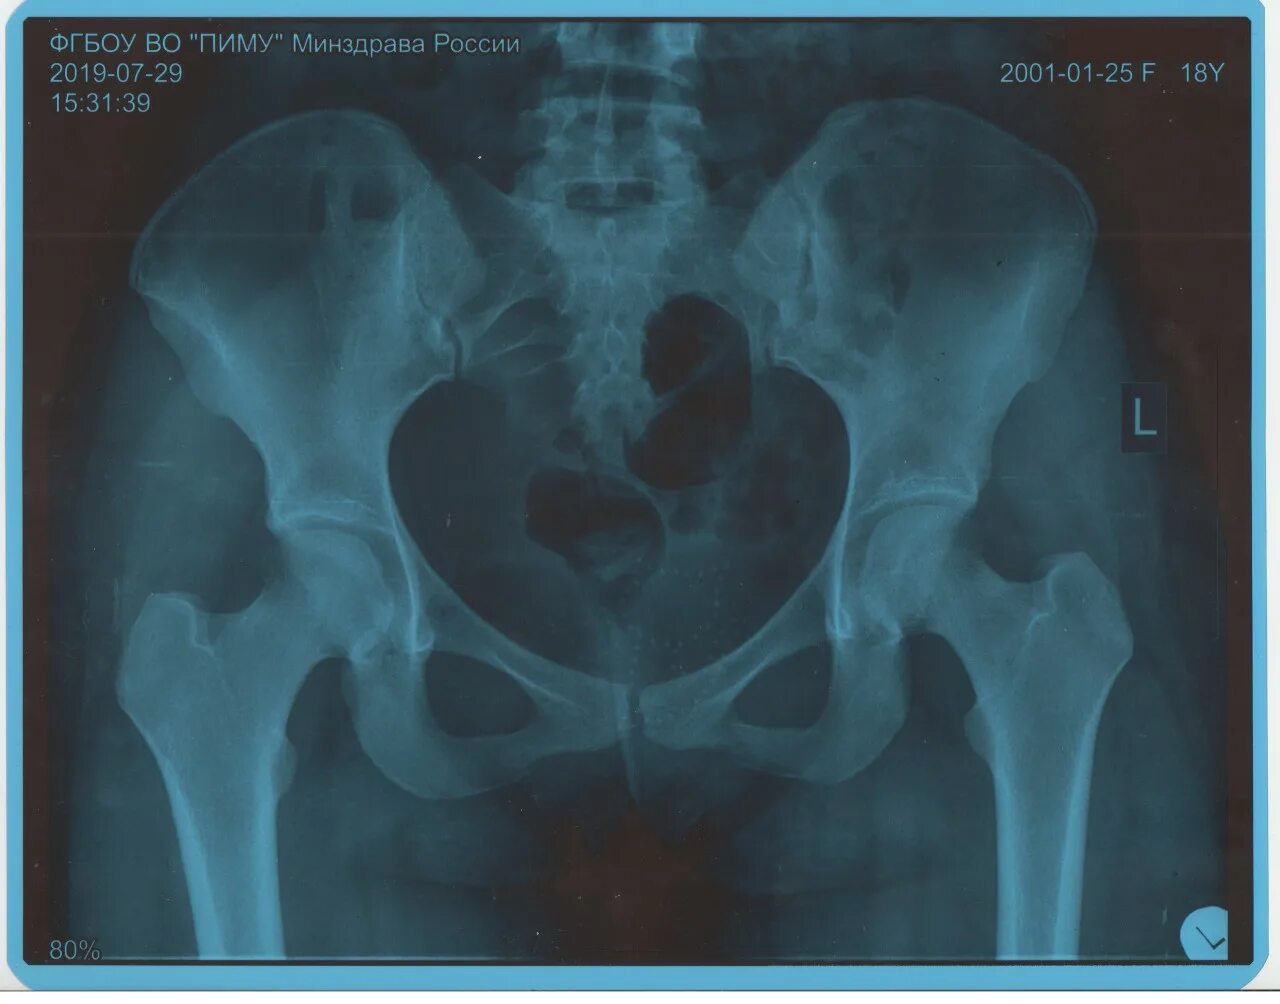

Снимок копчика